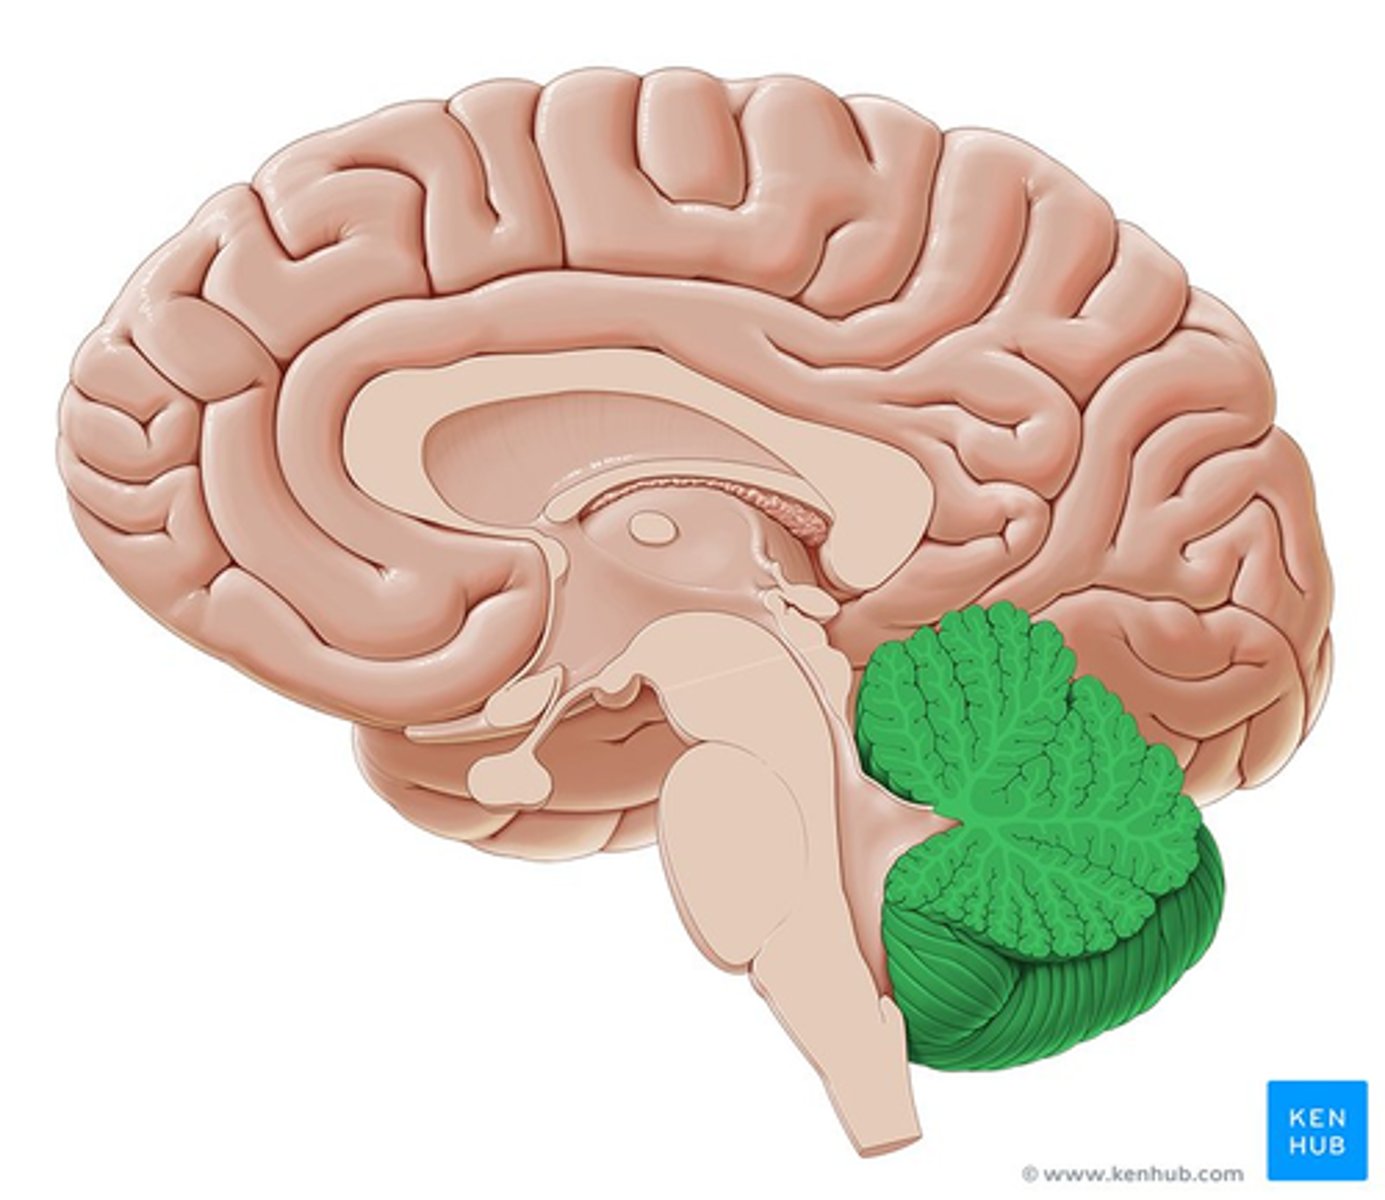

cerebellum